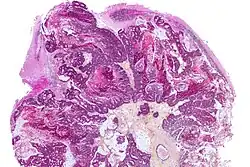

Brain - CT scan - Metastatic Pulmonary Adenocarcinoma. Arrow points to extensive edema of frontal lobe due to 23mm mass. Second area of edema can be seen in the left parietal-occipital region. - Genitourinary tract cancers, 11%